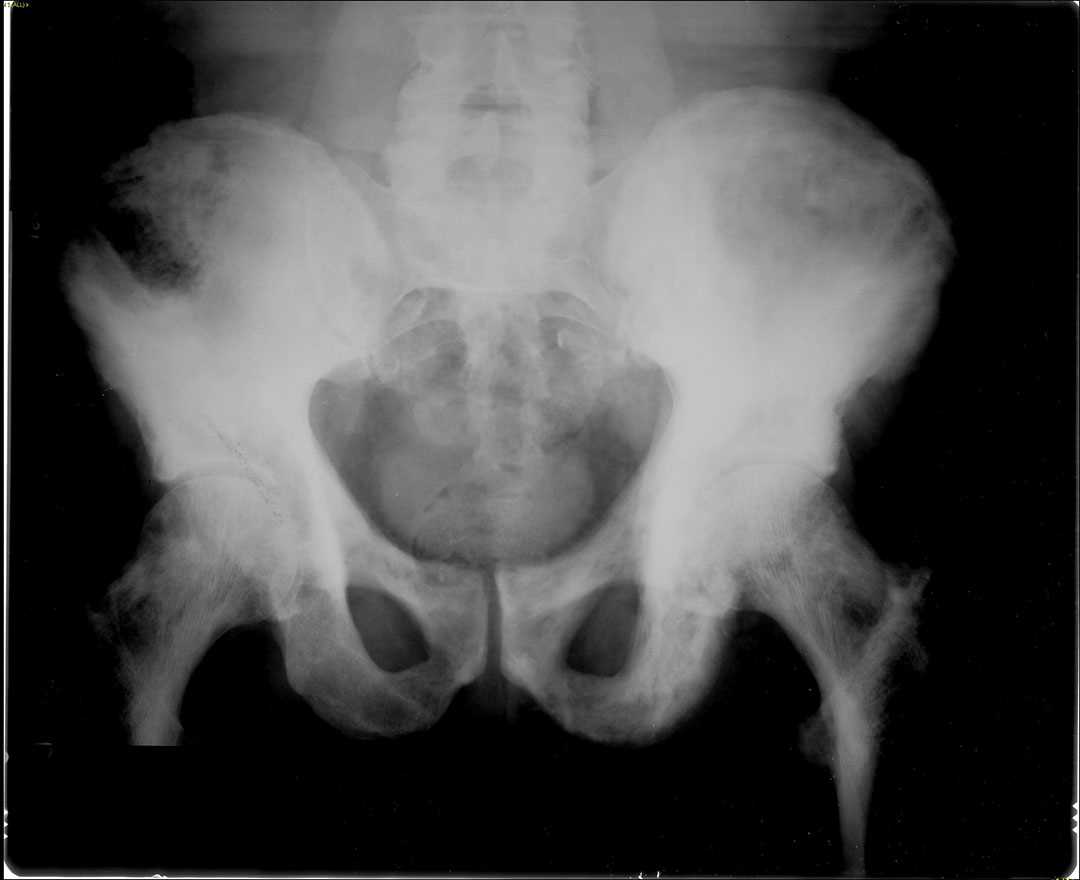

Paget's disease of bone, Xray Stock Image C021/3140 Science Paget's Disease Spine Radiology This article reviews the demographics, basic pathophysiology, natural history, and clinical presentation of. This article reviews the various spinal pathomechanisms and osseous dynamics involved in producing the varied imaging. The two main clinical manifestations of paget disease are pain due to the pagetic lesion in bone itself or from. The disease is polyostotic in 66% of cases and. Paget’s disease. Paget's Disease Spine Radiology.

Paget's Disease of Bone Sumer's Radiology Blog Paget's Disease Spine Radiology Paget’s disease (pd) is a common bone disorder of the aging population where the spine is the second most common involved location after the pelvis. The two main clinical manifestations of paget disease are pain due to the pagetic lesion in bone itself or from. Spinal stenosis in paget’s disease has the unique radiographic feature of widening. The disease is. Paget's Disease Spine Radiology.